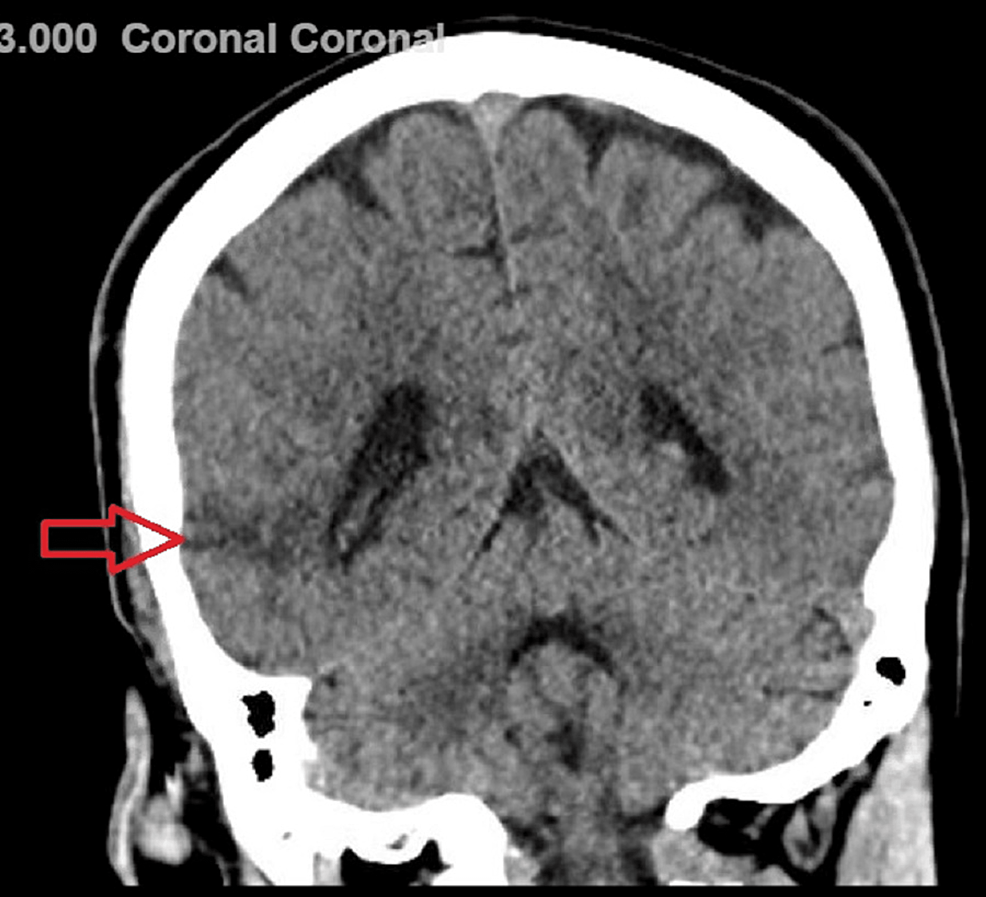

(a, b) A CT scan demonstrated a nodular, isodense, and necrotic mass in

Cureus A Unique Case of the Syndrome of Irreversible Lithium Indeterminate Meaning In Ct Scan indeterminate findings are imaging results that are not clear or categorizable. indeterminate lesions are detected on cancer imaging examinations at all points along the patient pathway. Find out how to get prior exams, compare. learn what a radiologist looks for and reports in an abdominal and pelvic ct scan, and what the terms mean. indeterminate lesions. Indeterminate Meaning In Ct Scan.